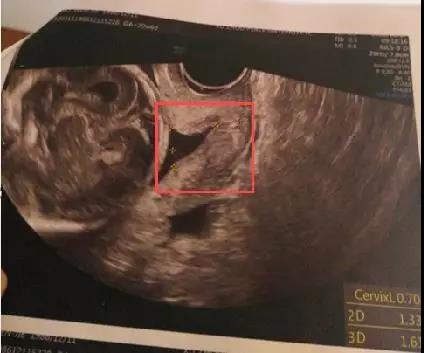

▲孕21周时彩超显示廖女士的宫颈长度仅剩7毫米

但多次宫腔镜手术让我隐隐担心宫颈机能。12周、16周时宫颈检查还正常,21周约了和平妇产台湾超声专家邱博士的E10彩超,一检查却发现内口已开,宫颈长度仅剩7毫米!非常危险,随时有流产的可能,情况紧急!